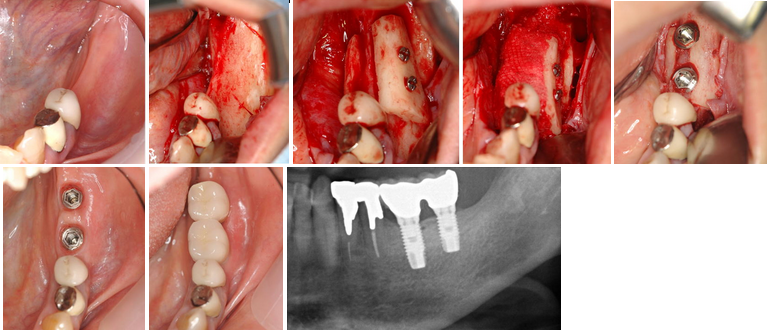

1.骨欠損がある1歯欠損症例(症例 3、自家骨移植症例)

下顎枝部から骨移植を審美的インプラント治療を行いました。

2.骨欠損がある2歯欠損症例(症例 4、自家骨移植と口蓋粘膜下結合組織移植)

かなり骨欠損があったが、下顎枝部から骨移植を審美的インプラント治療を行いました。歯肉の厚みを増やすために口蓋粘膜下結合組織移植も併用しました。